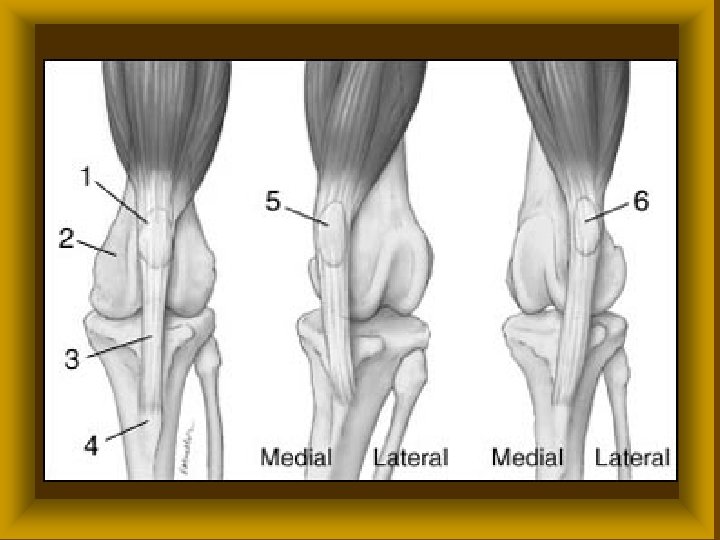

FICAM ( LUXATIO ) Ø Luxatio completa ( teljes ) Ø Subluxatio ( részleges ) Ø Veleszületett (csípőficam) Ø Szerzett * traumás * habituális * recidiv

Subluxatio

FICAM ( LUXATIO ) SZÖVŐDMÉNYEI ØIzületi tok, izmok szakadása ØBőr, ideg, érsérülések ØCsonttörés

FICAM ( LUXATIO ) TÜNETEI Ø Szubjektív fájdalom * működési zavar Ø Objektív * alakváltozás * rugalmas rögzítettség *

FICAM ( LUXATIO ) KEZELÉSE Ø Repositio ( narkózisban ) * konzervativ * műtéti Ø Rögzítés Ø Rehabilitatio